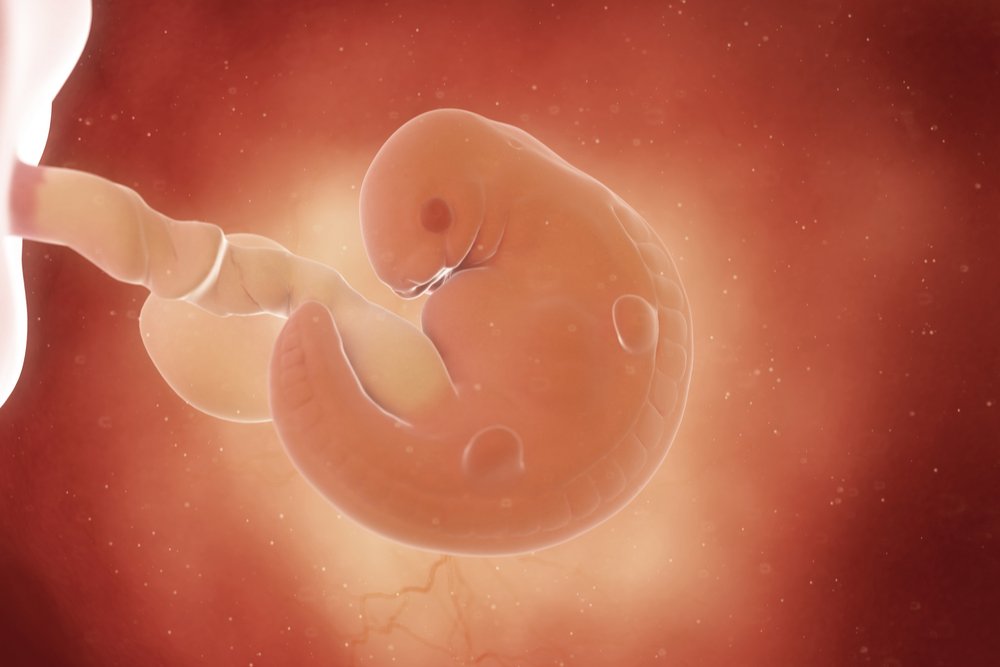

Формирование Плода в Первом Триместре: Важные Этапы